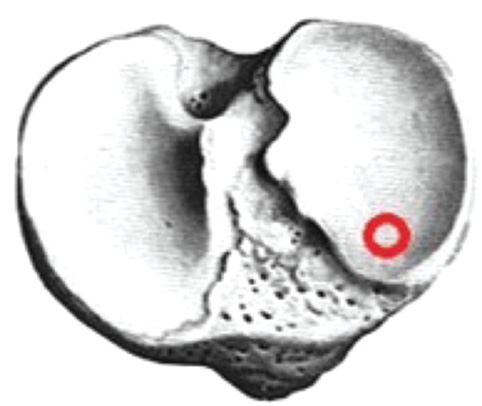

When forming the femoral channel, we focused on the posterior wall of the intercondylar fossa. In most cases, no problems were encountered during site selection for the formation of a new femoral channel. When the primary femoral channel was located anteriorly, a new channel was formed 2–3 mm posteriorly and no more than 7 mm in diameter (Fig. 6).

Fig. 6. Anterior location of the femoral canal, — correct channel placement.

If the femoral channel was located posteriorly, the new channel was displaced anteriorly, and a 6–7 mm-thick graft was used (Fig. 7).

Fig. 7. Posterior position of the femoral canal, — correct channel placement.

In some cases, the femoral channel was located high, so we make a standard intraosseous channel corresponding to the diameter of the resulting autograft (Figs. 8–10). At a low location, a new femoral channel was formed more proximal, and the channel was also centered on the tibia medially by 2 mm (Fig. 11).

Fig. 8. High position of the femoral canal, — correct channel placement.

Fig. 9. New intraosseous canal in the femur, malformed canal above.

Fig. 10. Final view after autograft.

Fig. 11. Low position of the femoral canal, — correct channel placement.